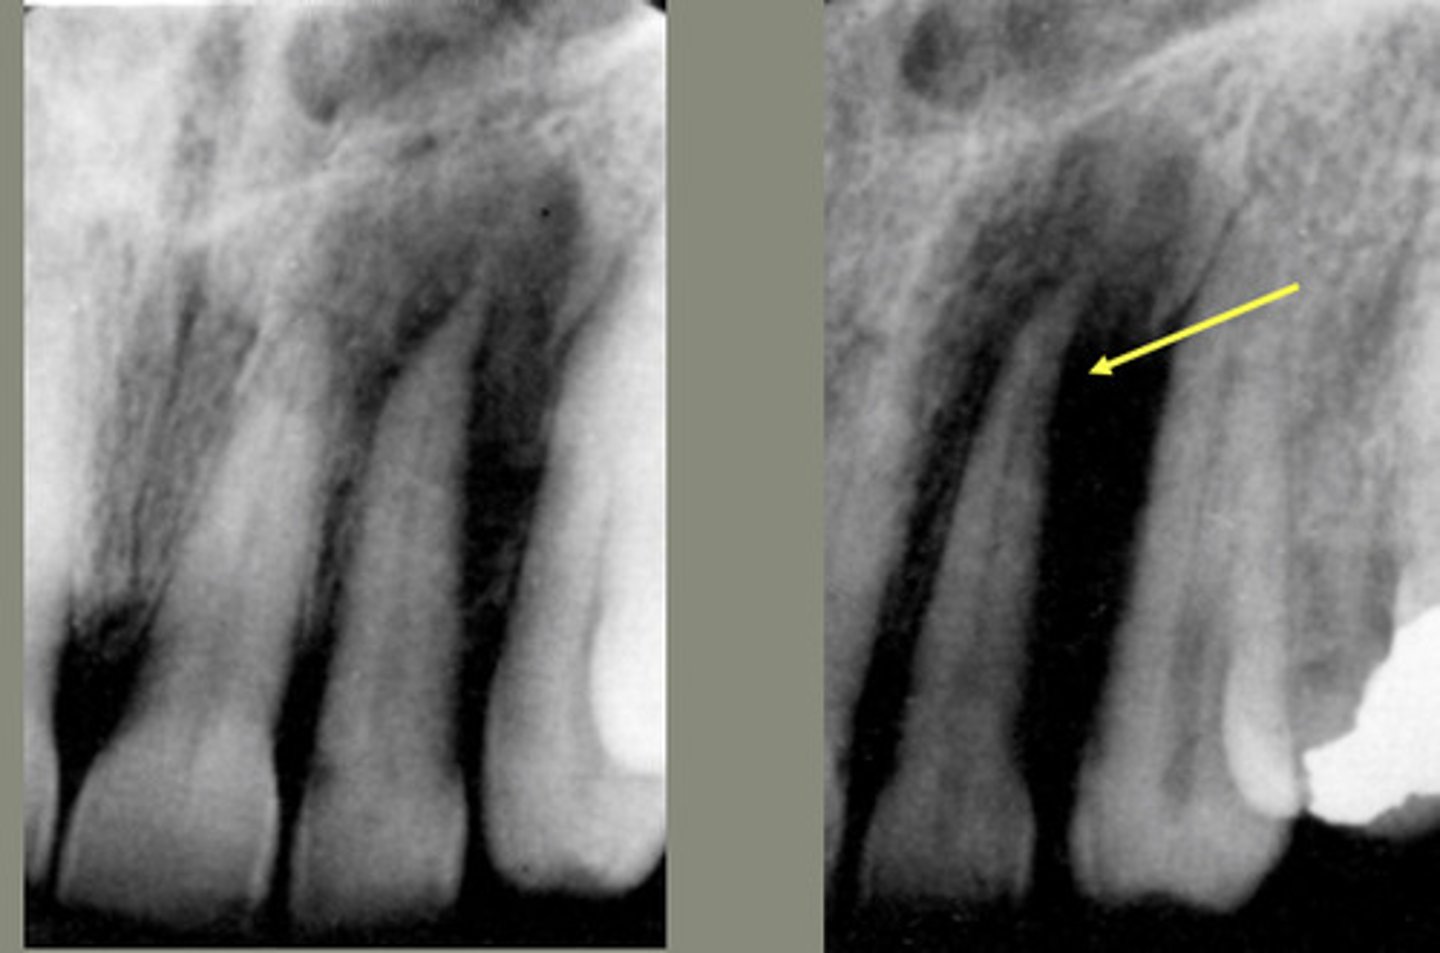

What characterizes asymmetric widening of PDL?

Loss of lamina dura